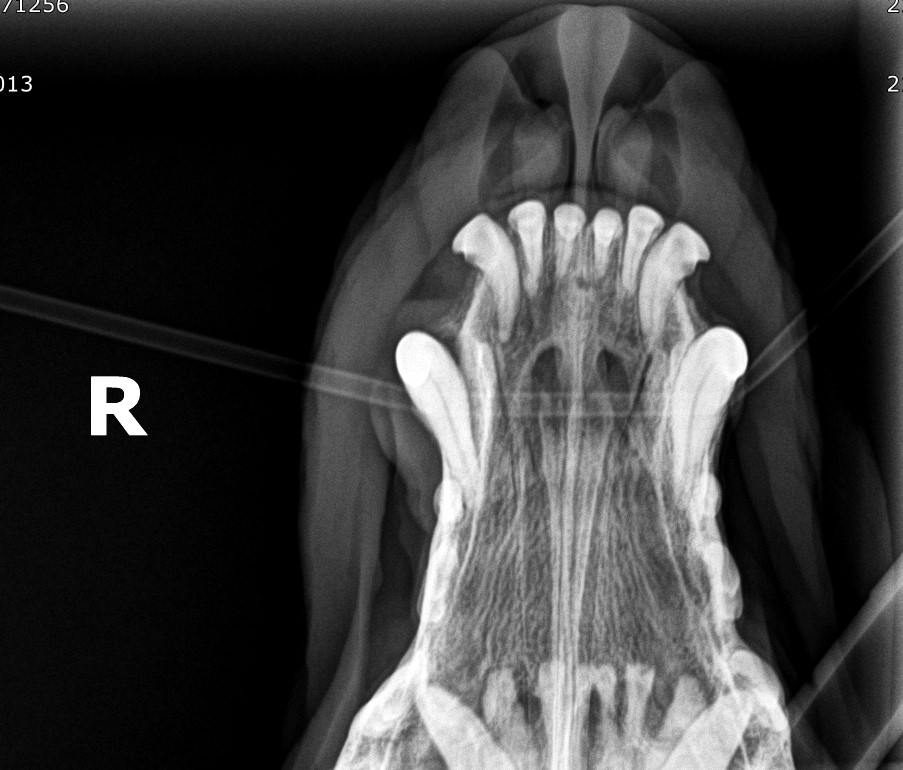

Representative occlusal radiographic view of the mandibles of a cat Cat Jaw X Ray It a mass (growth), that might be benign or malignant. 1,2 radiographs are essential for identifying and documenting the nature and severity of dental disorders and conditions. This cat has a problem with its lower jaw (mandible). You will be given examples of normal ones, and a given a chance to make a diagnosis on. Compare it to a normal. Cat Jaw X Ray.